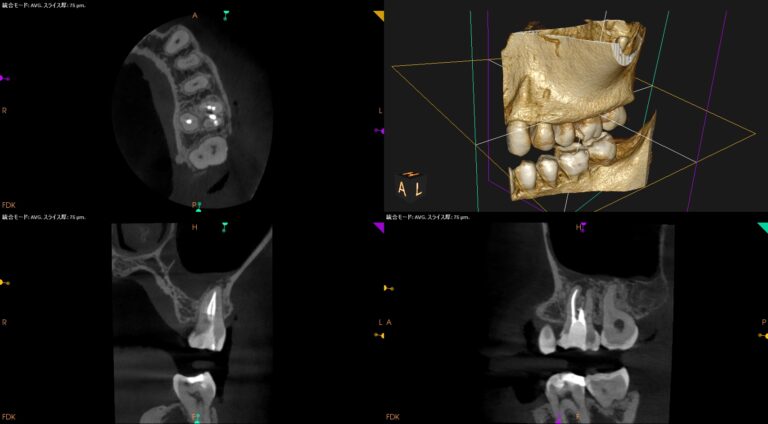

CBCT(2023.12.20)

MB

根切するには厳しい位置に#31のM根のApexはある。

穿通は必須である。

ML

MLには根尖病変と思しき透過像がそれほど顕著ではないが若干見える。

この歯を根切することは容易であろうか?

といえば、

このCT画像が語っていることは、

頬側の皮質骨は相当厚いという臨床的事実だ。

それがApicoectomyを困難にしているのだろう。

できれば、非外科的な歯内療法でマネージメントしたい。